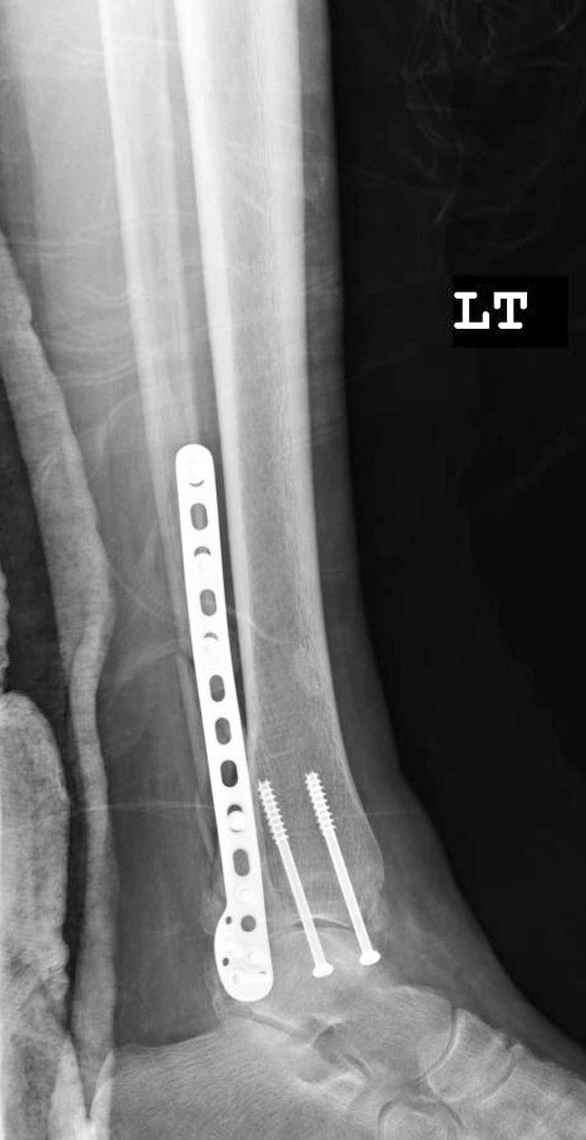

Здесь финальный снимок 73 летней с

сопутствующей шизофренией, латерально бридж

пластину (соединили дистальный конец с диафизом не трогая место перелома) и медиально перкутанно

двумя шурупами. В этам случае без гипса не

обойтись.

Как заметил, по рентгенограмме медиальная лодыжка не очень идеально репонирована. Больная кроме шизофрении страдала другими соматическими заболеваниями, и во время операции от анестезиолога получил рекомендацию поторопиться, поэтому решили закрыто, а так тенденция лечить